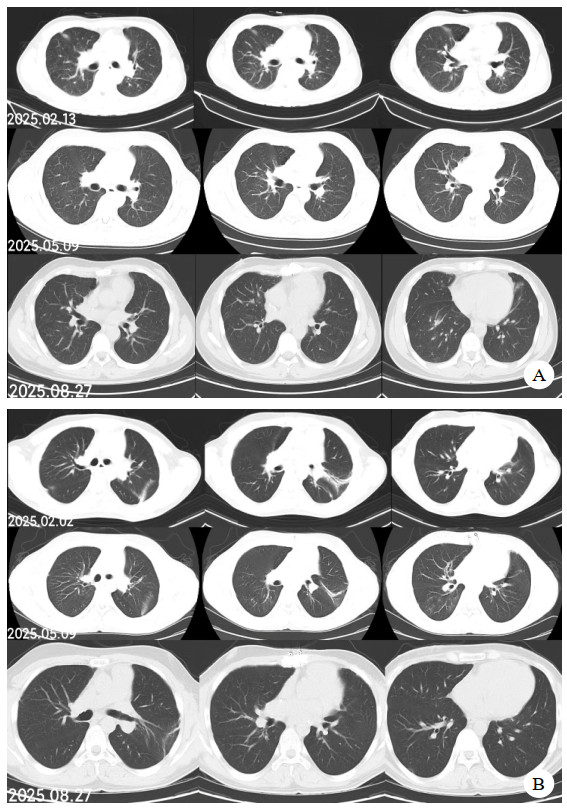

同时给予镇痛、镇静联合肌松,去甲肾上腺素泵入维持血压,俯卧位通气,B某入院后出现高热,经验性给予美罗培南联合万古霉素抗感染治疗,后降阶梯调整为哌拉西林他唑巴坦联合万古霉素治疗;C某抗感染方案为经验性使用万古霉素联合哌拉西林他唑巴坦治疗,痰培养出鲍曼不动杆菌后改为替加环素、头孢哌酮舒巴坦及万古霉素治疗;根据《刺激性气体中毒诊治专家共识》[5]中关于重症患者的治疗措施,同时给予2人泮托拉唑抑酸护胃,氨溴索、富露施化痰、甲泼尼龙抗炎、西维来司他纳及乌司他丁清除炎性介质,维生素C抗氧化、保肝、输血补液,纤支镜吸痰及肺泡灌洗,维持水电解质平衡及营养支持治疗,特别考虑到肺损伤情况,在使用有创通气时给予超保护性通气策略[5, 7];2人仍先后出现气胸、纵膈气肿,行胸腔闭式引流;持续V-V ECMO治疗15 d后,肺部纤维化不可逆转,高分辨率CT肺纤维化评分 > 75%(图 3、4),符合终末期肺病标准,有肺移植指征[8],经评估后2人顺利完成病变肺组织切除(图 5),双侧序贯肺移植,术后患者复查胸片肺部恢复正常(图 6),2位患者术后气管切管接呼吸机辅助通气,并给予泼尼松、他克莫司、吗替麦考酚酯抗排异治疗,其余根据病情给予万古霉素调节肠道菌群、抗感染、保肝、抗凝、呼吸康复锻炼等治疗,后顺利脱机、拔除气切套管,病情稳定出院,后续规律复查胸部CT(图 7)恢复良好。

| 注:图A为B某;图B为C某 图 6 患者肺移植术后胸片 |

| 注:图A为B某;图B为C某 图 7 肺移植术后第2个月、5个月、8个月CT影像 |